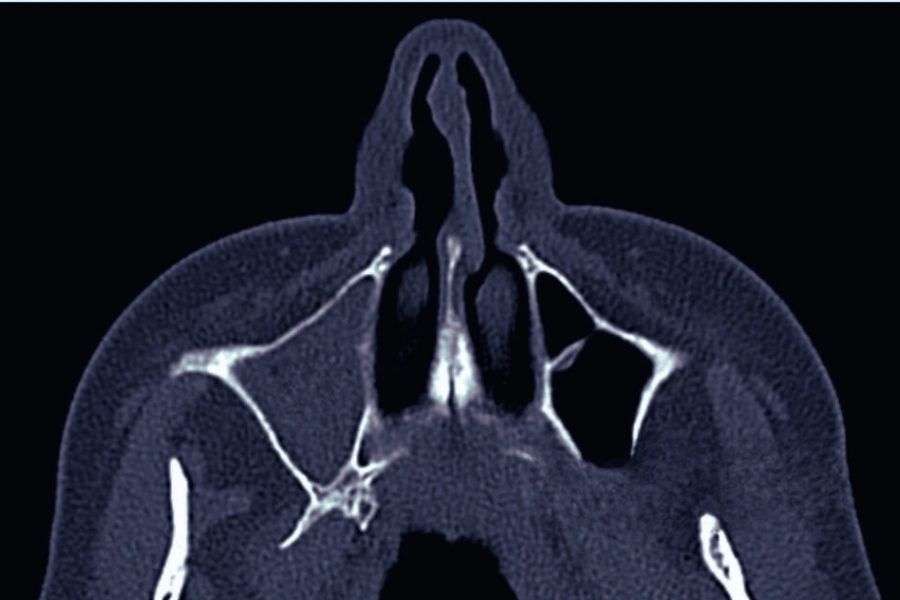

КТ пазух носа — це метод променевої діагностики, який дає змогу отримати максимально точне тривимірне зображення носової порожнини та навколоносових пазух. За допомогою комп’ютерної томографії лікар бачить навіть найменші зміни у структурі слизової, кісток або повітряних порожнин, що робить цей метод незамінним при підозрі на синусит чи поліпи.

Під час обстеження апарат робить серію тонких рентгенівських зрізів під різними кутами. Потім спеціальне програмне забезпечення об’єднує ці знімки у детальну тривимірну модель області обстеження. Це дозволяє візуалізувати навіть невеликі потовщення слизової, оцінити прохідність ходів між пазухами та побачити утворення, які не помітні на звичайному рентгені. Завдяки КТ лікар може роздивитися не лише поверхневі зміни, а глибинні патологічні процеси.

Синусит — це запалення слизової оболонки навколоносових пазух, яке може бути гострим або хронічним і проявлятися у різних формах залежно від ураженої пазухи: гайморит (верхньощелепна пазуха), фронтит (лобова пазуха), етмоїдит (ґратчастий лабіринт) та сфеноїдит (клиноподібна пазуха). На відміну від звичайного рентгену, комп’ютерна томографія дозволяє побачити не лише наявність і розмір запалення, а й детально оцінити всі найдрібніші структурні зміни, викликані захворюванням.

Однією з перших ознак синуситу, яку фіксує КТ носа, є потовщення слизової оболонки. У здорових пазухах слизова надзвичайно тонка, але при запаленні вона набухає, і навіть мінімальні зміни — у межах кількох міліметрів — добре видно на знімках. Це допомагає лікарю визначити, у яких саме пазухах (гайморових, лобових, клиноподібних чи ґратчастих) почався запальний процес.

Ще одним характерним проявом синуситу є наявність рідини або гнійного вмісту в пазухах. На КТ це виглядає як ділянки зі щільнішою структурою, що заміщують повітря. У гострих випадках може бути чітко помітна межа між повітрям і рідиною, яка вказує на активне запалення.

Крім цього, КТ навколоносових пазух дає можливість оцінити прохідність природних отворів між пазухами та носовою порожниною. Саме їх закупорка часто стає причиною хронічного синуситу — слиз не може нормально виходити, накопичується й підтримує постійне запалення.

Поліпи у носі або в навколоносових пазухах — це доброякісні новоутворення слизової оболонки, які часто виникають на тлі хронічного запалення або алергії. Їх поява зазвичай пов’язана з порушенням вентиляції пазух і постійним подразненням слизової. КТ пазух носа у цьому випадку є головним методом, який дозволяє визначити розміри, форму, розташування та поширеність поліпів, а також відрізнити їх від інших утворень — кіст чи пухлин.

На томографічних знімках поліпи виглядають як однорідні утворення низької щільності, що виступають у порожнину носової пазухи. Їх структура зазвичай рівномірна, без включень чи кальцифікатів, а контури — гладкі та чіткі.